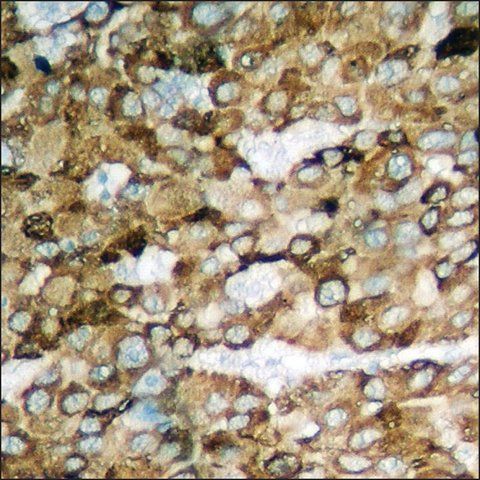

CANX (calnexin) is an endoplasmic reticulum (ER) chaperone. It has a molecular weight of 67kDa and is present in the endoplasmic reticulum. CANX is a type I transmembrane protein and is located on human chromosome 5q35.

The antiserum was produced against synthesized peptide derived from human Calnexin around the phosphorylation site of Ser583.

Immunogen Range: 543-592

CANX (calnexin) participates in protein folding and quality control. This gene is responsible for glycan-independent interaction and retention of mutated Gas3/PMP22 (growth arrest-specific protein 3/peripheral myelin protein 22) proteins involved in Charcot-Marie-Tooth 1A and Dejerine Sottas syndrome.

| technique(s) | ELISA: 1:5000 immunofluorescence: 1:100-1:500 immunohistochemistry: 1:50-1:100 western blot: 1:500-1:1000 |